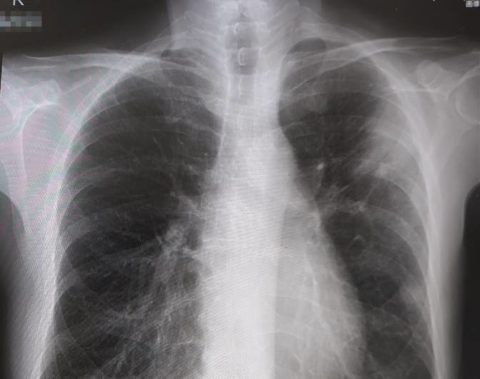

つい先日に肺炎を経験したこともあり、健康を守るためには仕方のない選択です。